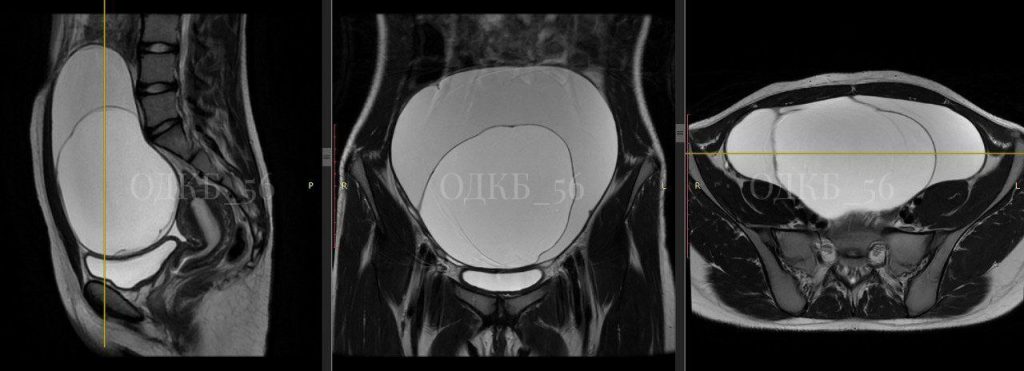

В октябре врачи ОДКБ провели сложную операцию 14-летней девочке. У нее обнаружили опухоль яичника, которая достигала 20 сантиметров в диаметре.

Школьница обратилась в больницу с острой болью. Девочку прооперировали в экстренном порядке.

Исследование удаленной опухоли показало, что образование доброкачественное, риска онкологии нет. Девочка восстанавливалась в течение недели.